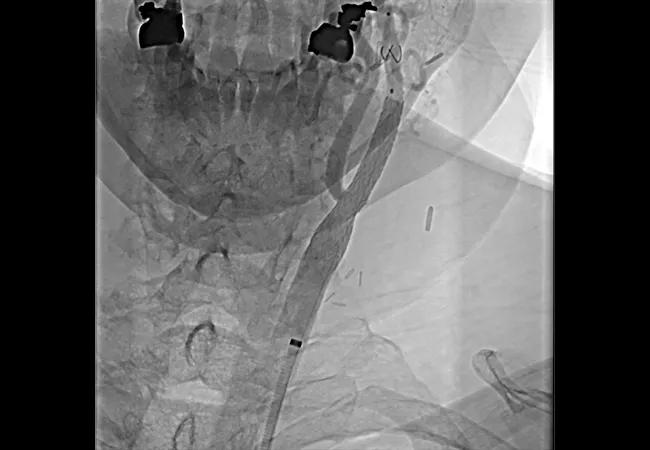

Advances Have Put Carotid Artery Stenting on Par With Surgery for Stroke Prevention

Outcomes of carotid artery stenting for stroke prevention in patients with carotid artery stenosis have reached parity with those of carotid artery surgery. So asserts a new JACC State-of-the-Art Review (J Am Coll Cardiol. 2022;80[2]:155-170), which attributes the parity to new techniques and devices, recent professional society statements promoting competency and improved understanding of appropriate candidate selection.

• Technology. New embolic protection devices, more stent options (e.g., dual-layered stents) and improved techniques have been developed.

• Patient selection. Preoperative risk assessment with CT angiography and magnetic resonance angiography has become important for assessing procedure risk by evaluating the aortic arch and branch vessel anatomy. High-risk features include vessel and arch tortuosity and dense lesion calcification. Patients over age 75 years are also deemed high risk for stenting.

“The evidence is now clear that carotid artery stenting is a reasonable and less invasive option than carotid endarterectomy for stroke prevention in patients with carotid artery stenosis,” Dr. Lyden notes. “However, it’s important that optimal strategies be employed, including the use of embolic protection devices, balloon sizing, efforts to ensure qualified operators, and appropriate candidate selection.”